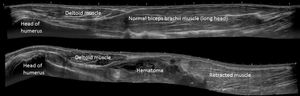

위팔두갈래근의 근위부 힘줄은 병적인 과정과 관련이 있으며, 어깨 앞쪽 통증의 흔한 원인이다.[18] 아래팔두갈래근 힘줄의 질환으로는 부착 부위 건염과 힘줄의 부분적 또는 완전 파열이 있다. 부분 파열은 일반적으로 통증, 비대, 그리고 힘줄의 비정상적인 윤곽으로 특징지어진다.[19] 완전 파열은 요골 결절에 부착된 이두근의 힘줄 부분이 박리되면서 발생하며, 종종 촉진 가능한 소리("팝" 소리)와 즉각적인 통증, 연조직 부종을 동반한다.[20]때로는 팔 앞쪽에서 연조직 덩어리가 발견되는데, 이를 소위 반전된 뽀빠이 변형(Reverse Popeye deformity)이라고 하며, 역설적으로 팔꿈치 굽힘 및 아래팔 뒤침 시 힘이 감소한다.[21]

위팔두갈래근의 파열은 운동 활동 중에 발생할 수 있지만, 원위 위팔두갈래근 힘줄의 박리 손상은 직업적인 성격을 띠는 경우가 많으며, 무거운 물건을 들 때 위팔두갈래근의 강하고 편심적인 수축 중에 발생한다.[20]

위팔두갈래근의 근위부 힘줄은 병적인 과정과 관련이 있으며, 어깨 앞쪽 통증의 흔한 원인이다.[18] 아래팔두갈래근 힘줄 질환으로는 부착 부위 건염과 힘줄의 부분적 또는 완전 파열이 있다. 부분 파열은 일반적으로 통증, 비대, 그리고 힘줄의 비정상적인 윤곽으로 특징지어진다.[19] 완전 파열은 요골 결절에 부착된 이두근의 힘줄 부분이 박리되면서 발생하며, 종종 촉진 가능한 소리("팝" 소리)와 즉각적인 통증, 연조직 부종을 동반한다.[20]때로는 팔 앞쪽에서 연조직 덩어리가 발견되는데, 이를 소위 반전된 뽀빠이 변형(Reverse Popeye deformity)이라고 하며, 역설적으로 팔꿈치 굽힘 및 아래팔 뒤침 시 힘이 감소한다.[21]

위팔두갈래근 파열은 운동 활동 중에 발생할 수 있지만, 원위 위팔두갈래근 힘줄의 박리 손상은 직업적인 성격을 띠는 경우가 많으며, 무거운 물건을 들 때 위팔두갈래근의 강하고 편심적인 수축 중에 발생한다.[20]